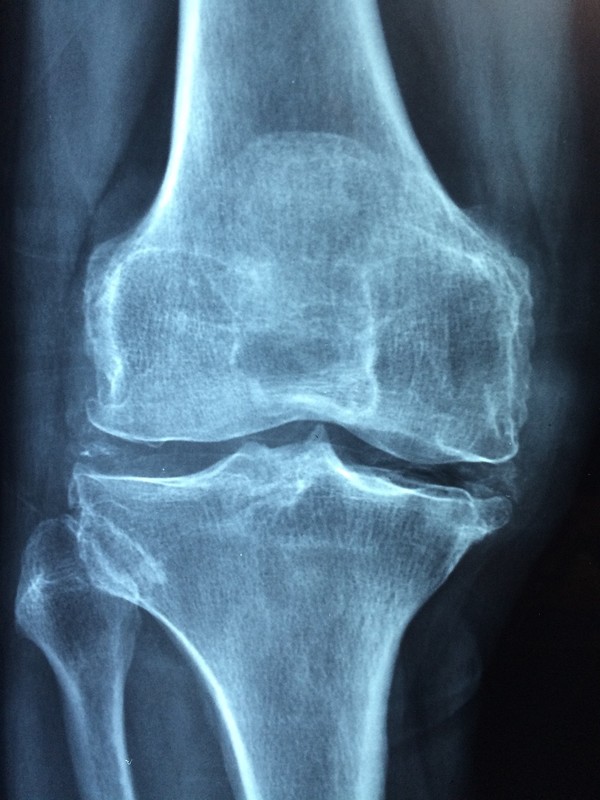

‘반월상연골판파열’도 자신의 체력과 관절 상태를 고려하지 않고 무리하게 운동을 할 경우 발병하는 질환 가운데 하나다. 주로 하체 중심 운동을 즐기는 사람에게 쉽게 발생하는 무릎 질환이다.

반월상연골판은 허벅지 부위 대퇴골과 정강이의 경골 사이 완충작용을 하는 반달 모양 조직이다. 무릎 연골이 찢어졌다는 것은 대부분 반월상 연골판 손상을 의미한다. 축구, 농구 등 급한 방향 전환이나 점프 또는 뛰어내리는 동작이 많은 운동을 할 때 발생 위험이 높다.

반월상연골판은 한 번 손상되면 재생이 어렵고, 방치하면 퇴행성 관절염으로 이어질 수 있다. 초기에는 주사, 물리치료 등 보존적 치료를 받으면 2~3개월 후 대부분 완화된다. 파열 정도가 크거나 완전 파열의 경우 관절내시경을 활용한 수술적 치료를 고려해야 한다.